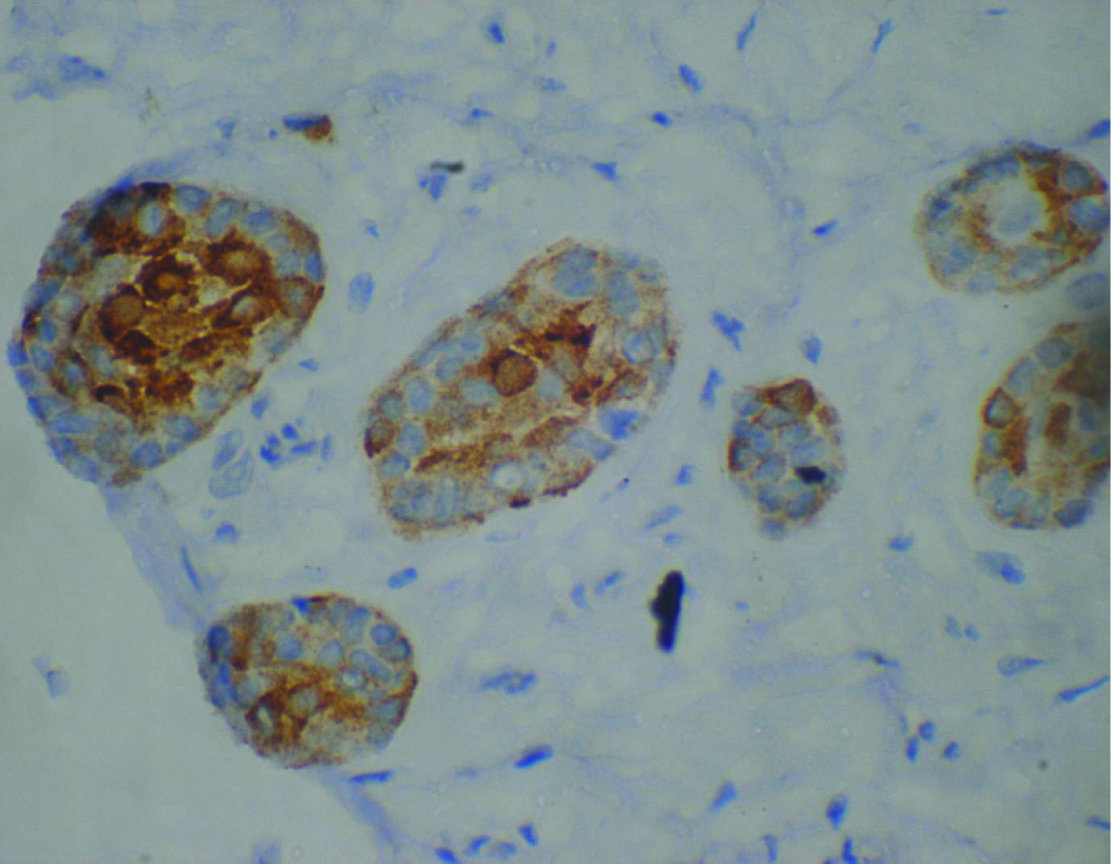

Intense ck-19 staining of the ameloblastic follicles 20x

Synaptophysin expression in ameloblastic follicles 20X

Diffuse positivity for nse in ameloblastic follicles –20x

CD99 staining in ameloblastic follicles 10x

All the 20 cases of Ameloblastoma studied [Table/Fig-4], showed a positive reaction to Synaptophysin [Table/Fig-3] and NSE [Table/Fig-4]. Of these, diffuse positivity was observed in all the 20 cases for NSE [Table/Fig-4] and in 16 cases for Synaptophysin [Table/Fig-3] as shown. Four of the cases showed patchy positivity for Synaptophysin. CD99 [Table/Fig-5] staining was observed in only six cases, of which, two were diffusely positive and the staining was faint to moderate, membrane or granular cytoplasmic.